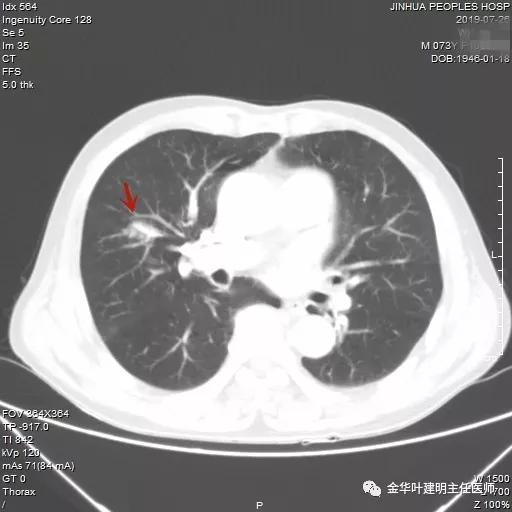

近日,同事再联系了我,说他同村的吴某已经决定来院接受手术治疗。所以就再次收住入院,予以复查了胸部CT增强,结果如下:

病灶较前有进展,更加膨隆了,直径也有所增加,好在仍未见明显纵隔淋巴结转移(特别肿大的淋巴结,但没有查PET评估)。其肺功能评估情况如下: